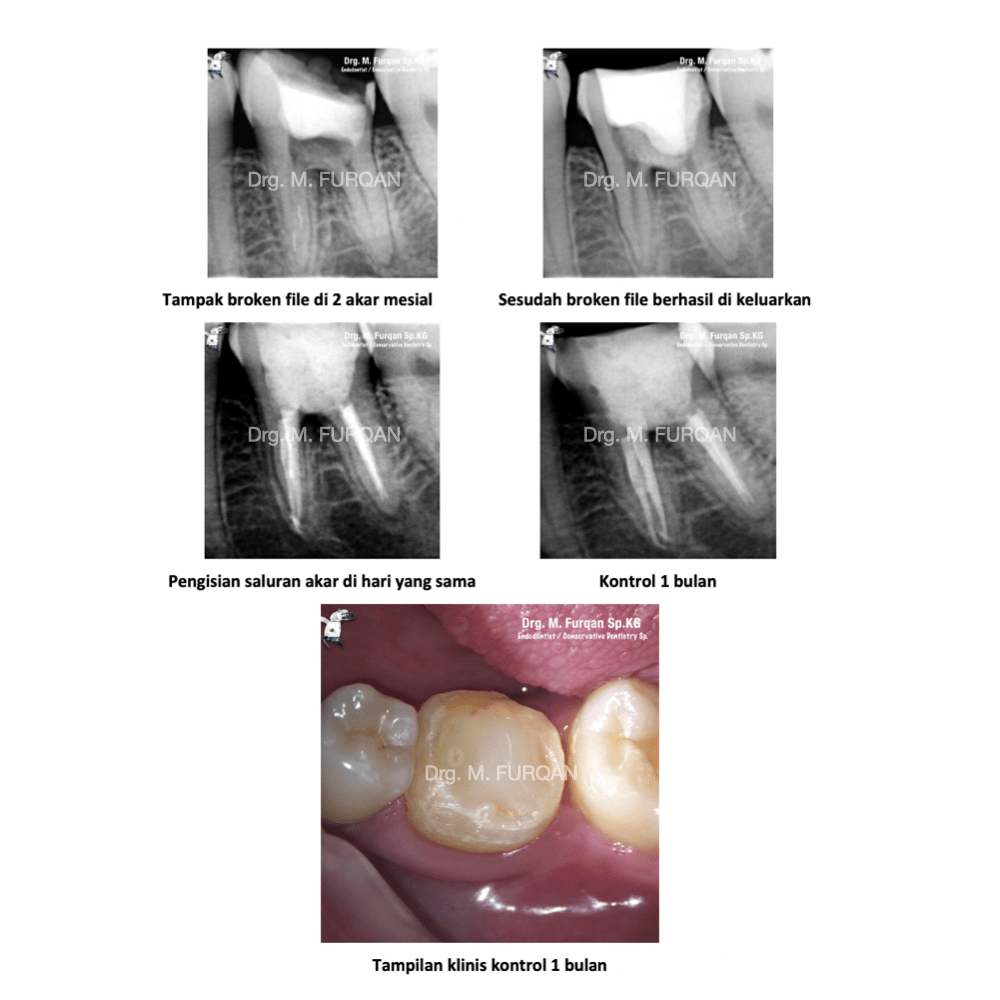

Perawatan saluran akar adalah salah satu perawatan yang berfungsi untuk menghilangkan atau memberhentikan sumber infeksi yang berkembang biak. Sering kali perawatan ini di sebut dengan perawatan saraf atau perawatan syaraf gigi, penggunaan nomenklatur ini dirasa kurang tepat. Tujuan lain dari perawatan saluran akar selain menghilangkan infeksi, perawatan saluran akar bertujuan mempertahankan gigi semaksimal mungkin didalam rongga mulut. Root Canal Treatment or Root Canal Therapy are The process of removing an infected, inflamed, or necrotic pulp and filling the residual space with an inert material. Access must first be gained to the pulp chamber and root canal system; the pulp canals are then measured and the pulp tissue and any infected material removed; the canals are then shaped, irrigated, and cleaned of debris; the root canals are obturated with a root filling material such as gutta-percha and a sealant, and finally a coronal seal placed to prevent bacteria from the mouth entering the root canal system. thank you for eighteeth dental and revoden asia using fast fill and fast pack to fiilling a root canals for more info you can visit my instagram https://www.instagram.com/furqan_rizal/ or contact my clinic +6281219972701